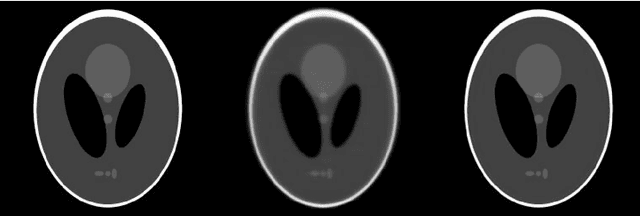

Abstract:Krylov subspace methods are considered a standard tool to solve large systems of linear algebraic equations in many scientific disciplines such as image restoration or solving partial differential equations in mechanics of continuum. In the context of computer tomography however, the mostly used algebraic reconstruction techniques are based on classical iterative schemes. In this work we present software package that implements fully 3D cone beam projection operator and uses Krylov subspace methods, namely CGLS and LSQR to solve related tomographic reconstruction problems. It also implements basic preconditioning strategies. On the example of the cone beam CT reconstruction of 3D Shepp-Logan phantom we show that the speed of convergence of the CGLS clearly outperforms PSIRT algorithm. Therefore Krylov subspace methods present an interesting option for the reconstruction of large 3D cone beam CT problems.